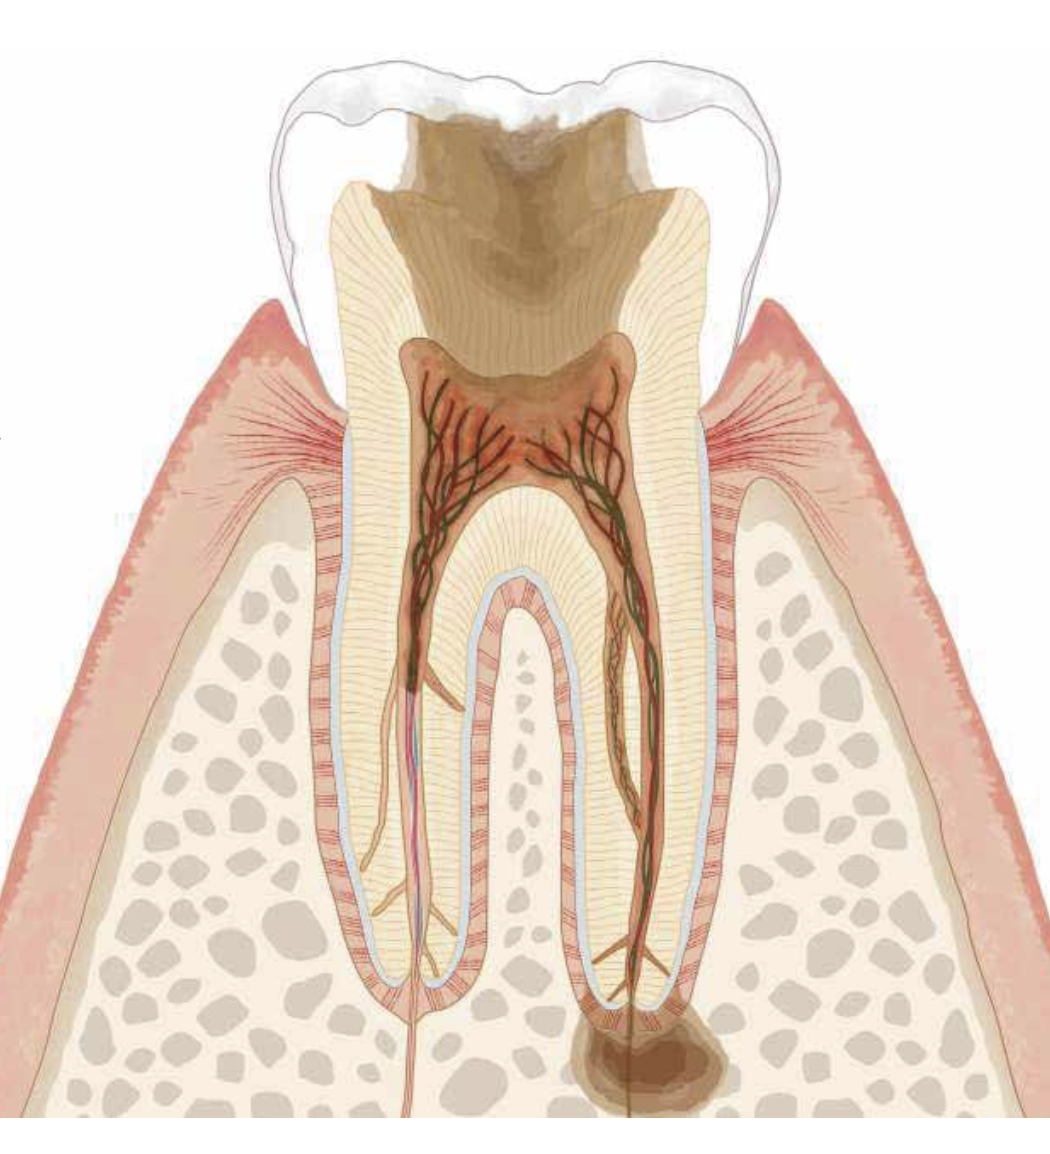

”根管治療”とは?

むし歯が根っこの中まで進んだ状態に対して行う治療です。

根の中には神経や血管などがあり、その部分の感染を除去する治療が根管治療です。